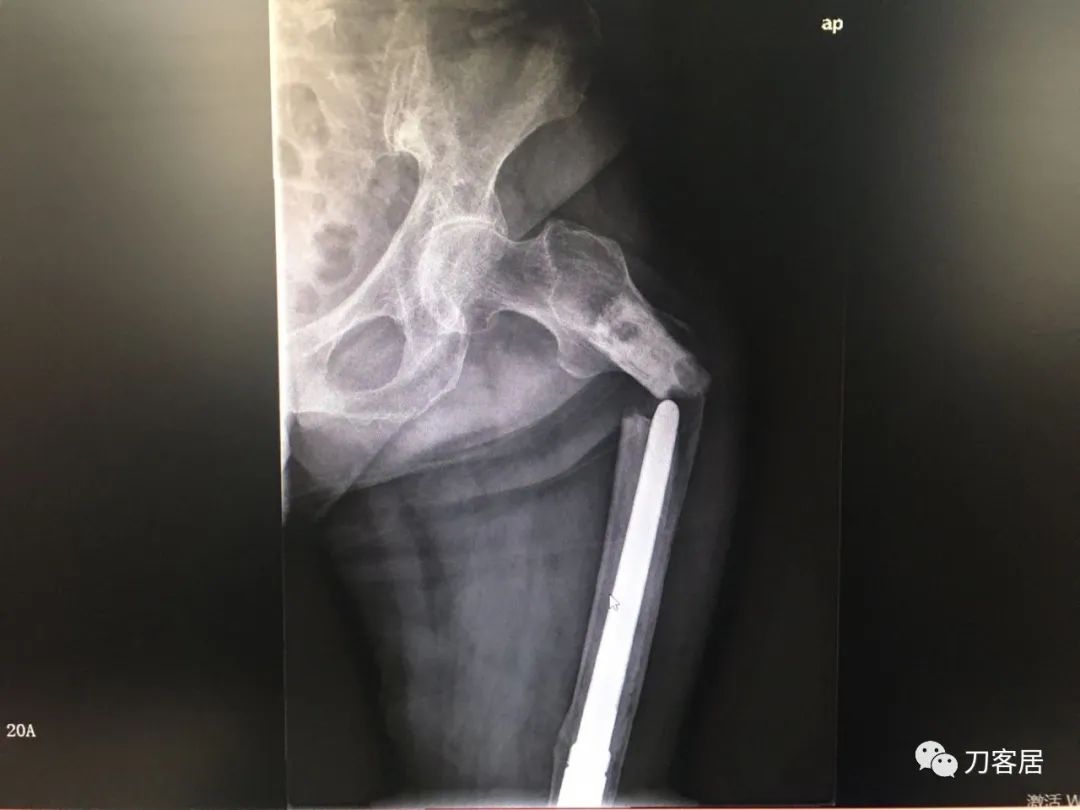

我不是中医黑2: 股骨髁上骨折,中药外敷治疗致股骨髁上陈旧骨折,县级中医医院手术,骨折病例用了骨肿瘤手术关节置换假体。

摘要: 这个病例第一次是摔伤致股骨髁上骨折,不知何种原因患者家属要求保守治疗,外包中药处理后骨折未愈合骨不连,后到一个县级中医院行了关节置换,选择的是肿瘤型假体。

现术后2年摔倒后致假体周围骨折。病人错误的选择,医生错误的治疗,最后导致不好的结局。

风吹麦浪10:25AM分享个病例,女性,67岁,外院手术后2年,现假体周围骨折。

风吹麦浪10:45AM这个病例第一次是摔伤致股骨髁上骨折,后不知何种原因家属要求保守治疗包中药处理后骨折未愈合骨不连,后到一个县级中医院行了关节置换,选择的是肿瘤型假体。

现术后2年摔倒后致假体周围骨折。

小土10:48AM患者第一次骨折的片子髌股关节好像不太好

何川11:05AM@长海医院刘忠堂同意,第一张片子显示髁上骨折,当时手术应该恢复最好。但后来拖成陈旧骨折不愈合,这对病人有教育意义。

何川2:58PM我是坚决反对这种病例一期做置换。如果,实在要做假体,要做好精细严密的术前计划,这是骨折病例,不是肿瘤,那些碎掉的骨块完全可以利用起来,延长杆就不需要用很长了。

从X片看没有涉及副韧带止点,可以保留重要骨块,加内固定钢板辅助,非限制性假体即可,实际用了铰链、这么长的杆,全髓腔骨水泥,基本打定主意一锤子买卖,把自己后路全断了。